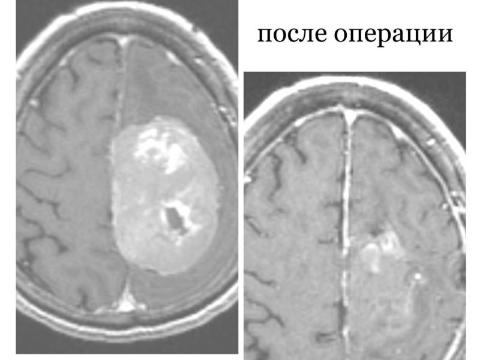

В мае 2024 года в Республиканскую клиническую больницу поступила 76-летняя женщина с жалобами на слабость в павой ноге и руке и на нарушение речи. Врачи выяснили, что пенсионерке диагностировали еще в 2018 году объемное образование в головном мозге и рекомендовали сделать операцию. Однако женщина и ее родственники были против вмешательства.  Пенсионерку выписали домой, и она на шесть лет забыла о своем заболевании.

В это время опухоль медленно росла, не доставляя забот, пока не начала сдавливать мозг.

- Поступила пациентка, которая не могла двигаться, у нее было спутано сознание, нарушена речь. Мы сразу же приступили у противоотечной терапии.    Переговорили с родственниками и они, наконец-то, дали свое согласие на операцию» - рассказал нейрохирург РКБ Булат Цыбиков.

Хирургическое вмешательство по удалению крупной опухоли головного мозга прошло успешно.